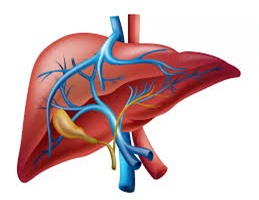

A liver transplant is a major surgical procedure that replaces a diseased, failing liver with a healthy one from a deceased or living donor. It is primarily used to treat acute…

A liver transplant is a major surgical procedure that replaces a diseased, failing liver with a healthy one from a deceased or living donor. It is primarily used to treat acute…

Liver resection (hepatectomy) is a surgical procedure to remove part of the liver to treat tumors (cancer or benign) or diseased tissue. Because the liver can regenerate, the remaining portion usually…